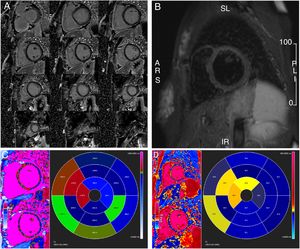

Transthoracic echocardiography. Bull's eye plot of left ventricular longitudinal strain showing (A) impaired values of basal walls in the acute phase and (B) their recovery one month later. ANT: anterior wall; ANT_SEPT: anteroseptal wall; INF: inferior wall; LAT: lateral wall; POST: posterior wall; SEPT: septal wall.

Transthoracic echocardiography findings indicating impaired basal left ventricular systolic function with basal ballooning in the acute phase and resolution of findings one month later.

| TTE findings | Acute phase | One month later |

| LVEDD (mm) | 56 | 47 |

| LVESD (mm) | 43 | 33 |

| LVEFa | 47% | 63% |

| LV GLS | -19%Impairment of basal segments | -21% |

| MR | ModerateCentral jet direction, apical displacement of leaflet coaptation point | Trivial |

GLS: global longitudinal strain; LV: left ventricular; LVEDD: left ventricular end-diastolic diameter; LVEF: left ventricular ejection fraction; LVESD: left ventricular end-systolic diameter; MR: mitral regurgitation; TTE: transthoracic echocardiography.

One month later, repeat TTE revealed LV recovery (LVEF 63%, GLS -21% with apparent improvement in basal segments, trivial MR) (Figure 1B, Table 1 and Video 1). Meanwhile, cardiovascular magnetic resonance showed no late gadolinium enhancement and normal T2-weighted short tau inversion recovery imaging, while T1 and T2 mapping were consistent with low-grade edema at the basal septum where systolic dysfunction was noted in the acute setting (Figure 3). Indexed LV end-diastolic and end-systolic volumes were 110 ml/m2 and 33 ml/m2, respectively (LVEF 70%).

Cardiovascular magnetic resonance one month after the acute phase. (A) Gadolinium study with no late enhancement; (B) T2-weighted short tau inversion recovery imaging showing no residual macroscopic myocardial inflammation or edema; (C) T1 mapping study and (D) T2 mapping study showing low-grade septal edema.